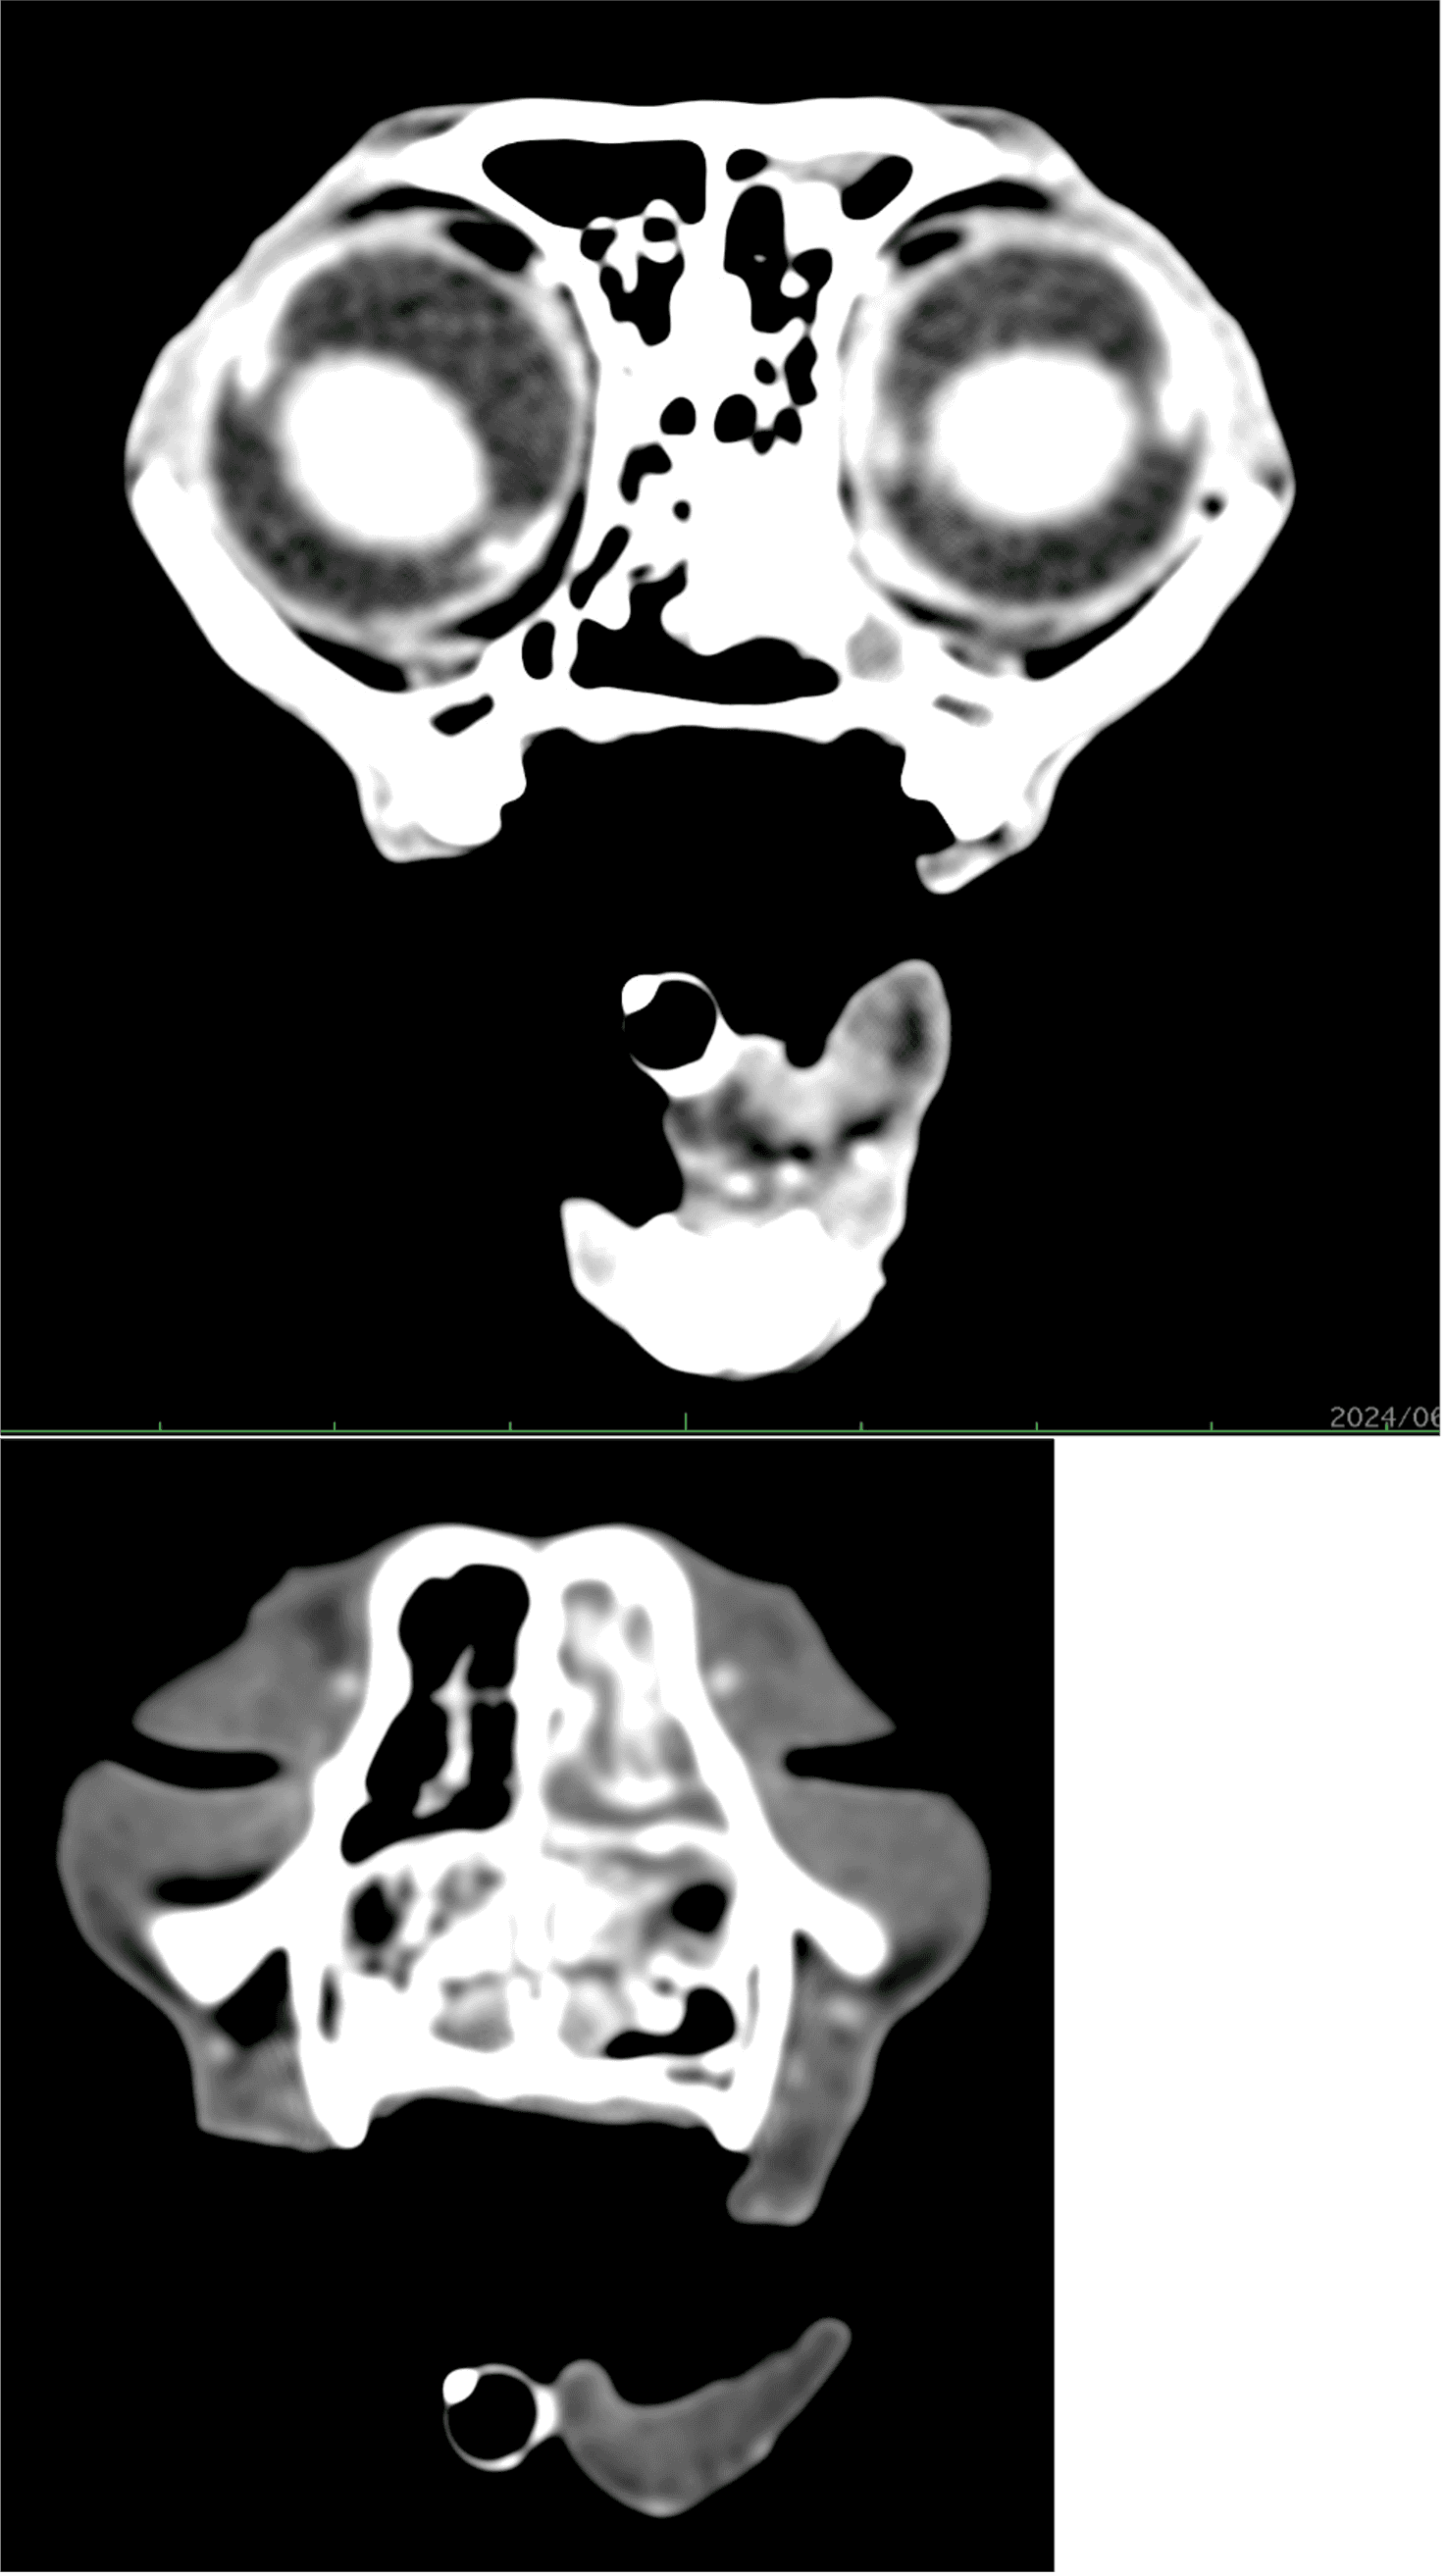

体重3.28kg(BCS3/5) 体温38.7℃ 心拍数160回/分 呼吸数28回/分 一般状態 :活動性100% 食欲100% 意識レベル 正常 一般身体検査 :左鼻より黄色鼻汁あり 左目の流涙あり 血液化学検査:特筆すべき異常所見なし 頭部CT(図1参照) 腹部超音波検査:左右腎臓の腎結石あり、その他諸臓器に特筆すべき異常所見なし

第5病日より放射線治療を実施した。照射プロトコルは1回8Gy 週1回 合計4回照射 総線量32Gyとなった 放射線治療の終了後、治療評価のためCT撮影を実施した。照射後CTでは大部分の病変は消失しているが、一部でびまん性病変の残存が疑われた。(図2)以上の所見より、放射線治療後残存したリンパ腫に対して化学療法を実施した。化学療法プロトコルは改変型COP療法とし、3ヵ月間継続した。治療後の経過は良好であり、現在化学療法終了から1年3ヵ月経過するが再発や転移は認められず、寛解を維持している。